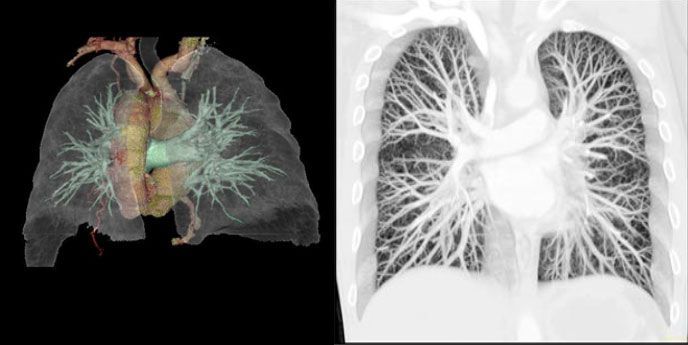

![]() |

| Рис.1. 3-D реконструкция коронарных артерий при МСКТ. Визуализируются ствол ЛКА, ПМЖА, ПКА по всей длине. |

А) достоверно визуализировать коронарные артерии [2,3, 4,18], с уточнением локализации атеросклеротического поражения, выявления аномалий развития венечных сосудов сердца (рис №1,5,17).

Визуализация атеросклеротического поражения коронарных артерий с помощью МСКТ является альтернативой инвазивной коронарографии (КАГ) (рис № 5) и используется как при доказанной ИБС [2,3,12,40], при подозрении на ИБС, так и у асимптоматических больных [2,14,67] с целью диагностики, выявления групп риска и определения их дальнейшего прогноза.